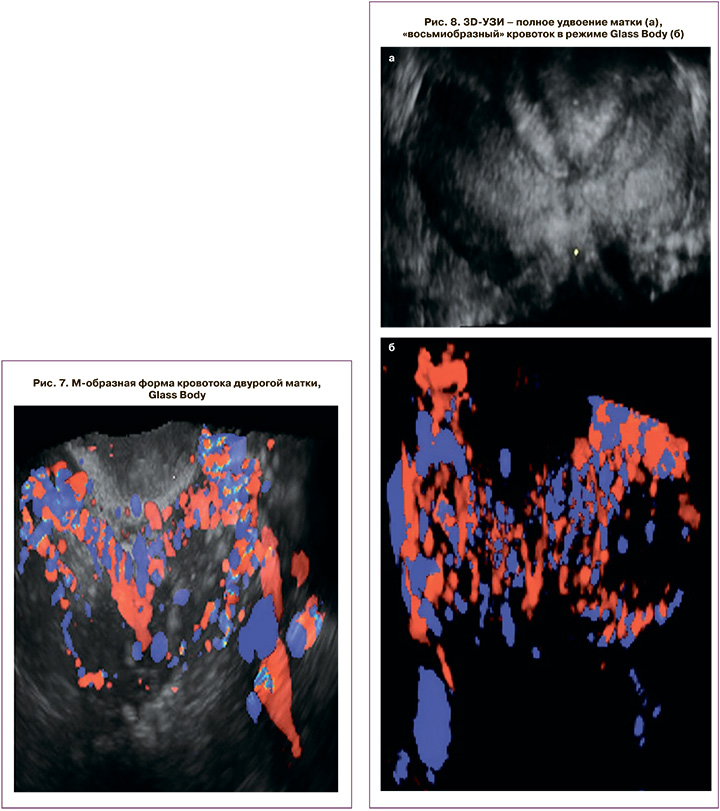

Трехмерными паттернами двурогой матки (класс U3a) стали: измененная форма тела матки за счет инвагинации НКМ глубиной от 2,5 до 16 мм, V/Y-образная форма полости. При наличии Y/V-образной формы полости и незначительном изменении НКМ измеряли расстояние от интеркорнуальной линии до НКМ, если оно было менее 4 мм, ставился диагноз «двурогая матка», если больше 4 мм – «внутриматочная перегородка». В зависимости от протяженности перегородки выделяют полную и неполную формы, однако, вне зависимости от ее формы, коррекция порока при помощи гистерорезектоскопии сопряжена с высочайшим риском перфорации матки. При неправильной интерпретации порока и диагностировании перегородки эндоскопический ориентир – устья маточных труб – будет ошибочным и произойдет непреднамеренная перфорация в проекции инвагинации НКМ, которая находится на линии, расположенной ниже устьев маточных труб. Такой редкий порок, как полная двурогая матка с удвоением шейки, диагностирован у 2 пациенток (рис. 6).

Режим Glass body позволил нам получить характерную архитектонику кровотока в виде M-образной формы, что разительно отличает порок от удвоения матки (рис. 7).

Удвоение тела матки (класс U3b) характеризуется прерывающимся и вновь восстанавливающимся НКМ, разделенным инвагинацией различной протяженности и глубины (от 5 до 7 см), зеркальными Г-образными формами гемиполостей. Glass Body позволил нам диагностировать «восьмиобразный» тип кровотока, свидетельствующий о полном равнозначном удвоении (рис. 8).